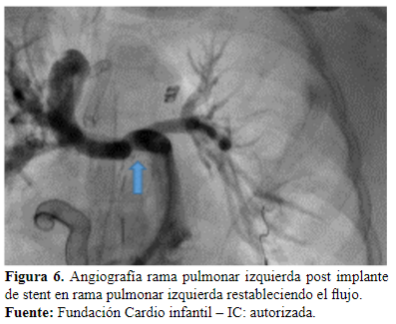

Dos días después es llevada a cateterismo cardíaco para ampliar estudios, donde se evidencia estenosis en la unión de la rama derecha con el conducto (Figura 4). Se realiza angioplastia con stent, queda con buena luz y buen flujo en el pulmón izquierdo (Figura 5y 6).